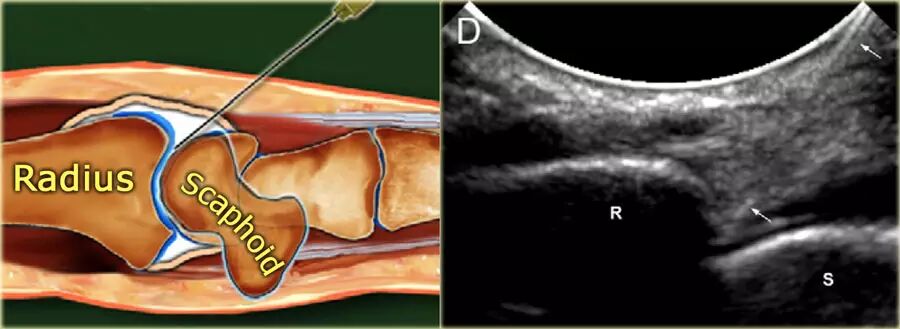

腕关节和手

桡腕关节     患者仰卧,手腕靠在45°海绵或卷起的毛巾上。在一些情况下,将手腕保持在尺骨偏离中可能是有帮助的,以便更多地打开关节空间。

在超声波上识别桡骨和舟骨之间的空间。在超声引导下,将23-25号,30mm针推进到指向半径的关节表面的关节中,直到感觉到与桡骨接触。在确保针的尖端没有刺入软骨中,注射2-4mL对比度。针的斜面面向关节空间,并且看到对比度流入关节。